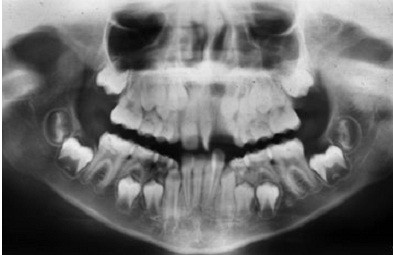

女,十岁,单侧唇腭裂致21牙、22、12牙畸形,且21牙、22牙间牙槽骨发育不全。经自体髂嵴骨移植后,拔除21牙、22牙行正畸治疗以将23牙移动至22牙位置。同时将正畸需拔除的下颌第一前磨牙移植到21牙的牙槽窝内。并在正畸治疗结束后树脂恢复21牙、22牙形态。患者18岁时拔除左上颌乳尖牙行种植义齿修复。